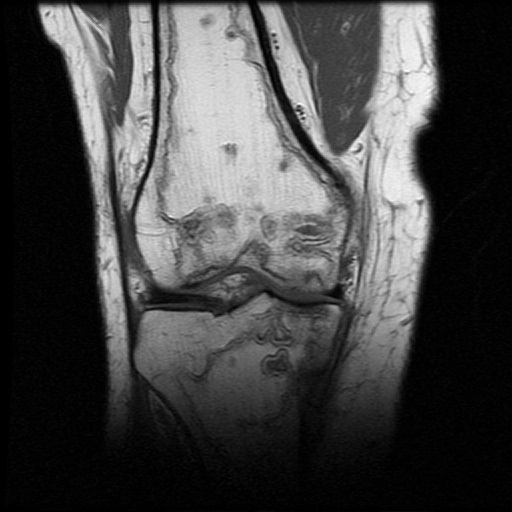

MULTIFOCAL OSTEONECROSIS

This is a condition characterized by widespread necrosis (dying) of the bone marrow in multiple bones. It is mostly caused by steroid use, but disorders of blood clotting, renal failure, auto immune disease, multiple sclerosis and HIV can all cause the condition. Treatment is aimed at the underlying cause and focal management of orthopaedic problems. Below are pictures of one of my patients with typical manifestations of the condition. His only risk factor seemed to be daily descent of 2.9 km into the mine using a very fast cage system.

His only symptom was knee pain. This was due to collapse of the bone deep into the cartilage. I implemented treatment of a total knee replacement using long stemmed implants to achieve stability in the necrotic bone.